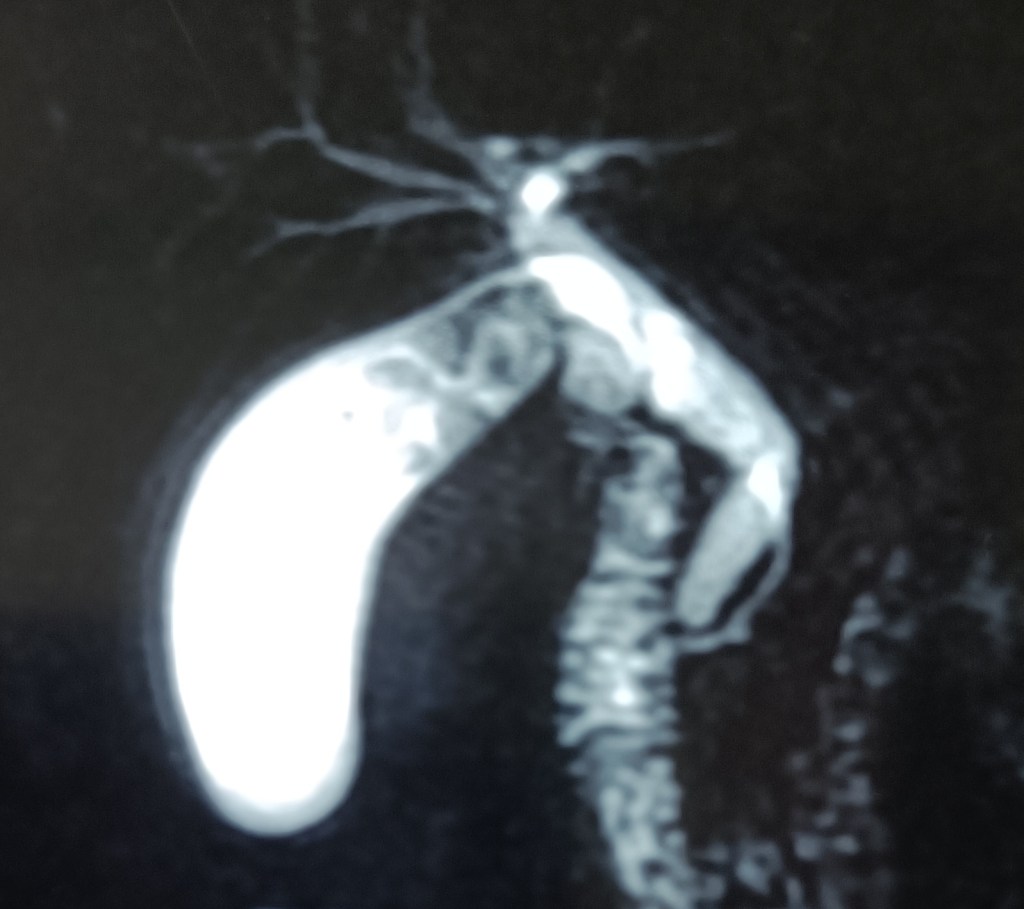

Amrik Singh 78 years old male (c/o dr Mohi). Big distended gall bladder, the fundus was palpable well below the costal margin (ram-horn gall bladder?). MRCP showed a long cystic duct, but at surgery, dense omental adhesions were found and removed with the help of harmonic scalpel, and the gallbladder was emptied first of its load of multiple big stones. The cystic duct could still not be clearly defined. Therefore, the gallbladder was ligated at its neck, and removed piecemeal.